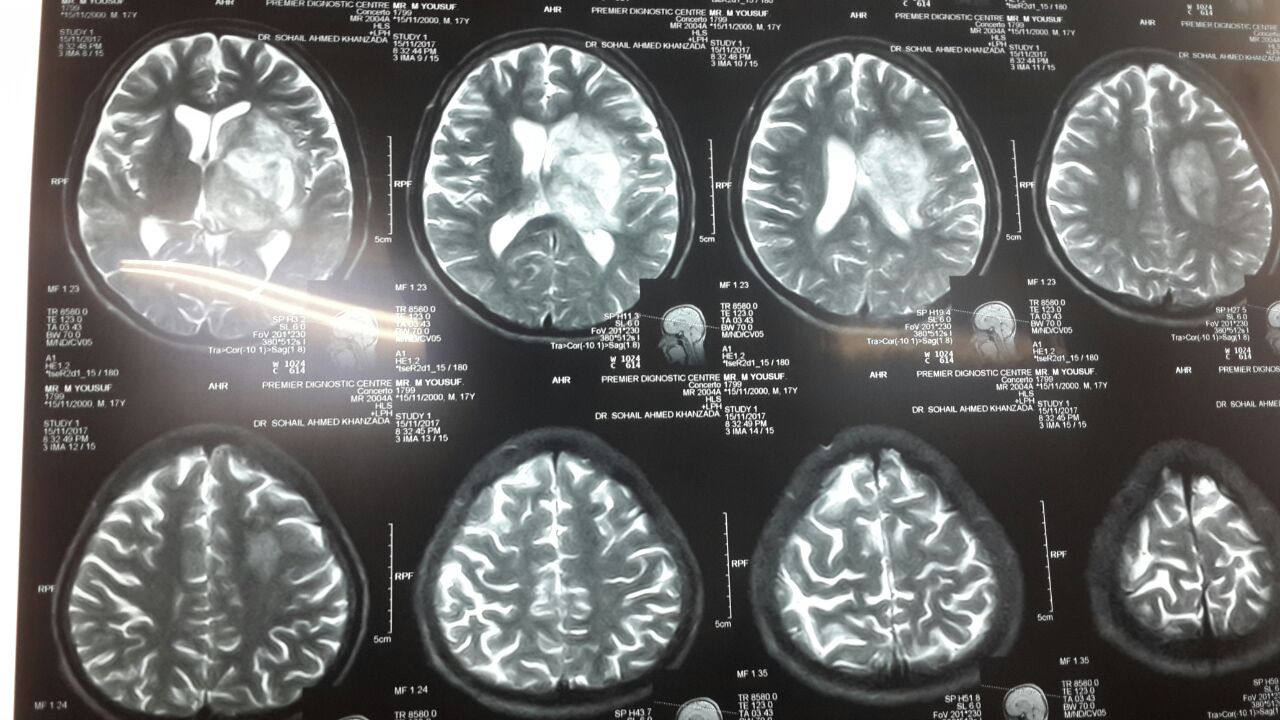

Случай 114. #мозг #МРТ #ОбучающиеМатериалы

Пациент К., 31 год. Пациент из урологии, направлен на МРТ неврологами с подозрением на энцефалит. Многоочаговое поражение мозга с накоплением в очагах по кольцевидному или паренхиматозному типу (илл. 1 и 2). При этом видно, что поражение активно вовлекает базальные ядра, таламусы. Весьма типична картина на DWI (илл. 3), особенно в сочетании с ADC (илл. 4).

В этой связи можно не только с большой уверенностью высказываться об энцефалите (молодой пациент, клиника энцефалита, характер поражения мозга). Но, даже, уверенно предполагать именно токсоплазмоз. Очевидно, что нужно искать сильнейшую иммуносупрессию. Собственно она и была подтверждена после обсуждения МРТ с неврологами на консилиуме (пришел положительный ВИЧ).

Хотелось бы обратить внимание на странную формулировку заключения (илл. 5). Имеется типовая проблема, частный случай так называемой ошибки основания деления. «Специфическое» воспаление - один из вариантов воспалительного процесса вообще. Таким образом не понятно что предлагается дифференцировать в этом заключении. Кроме того, абсцесс - всегда воспалительного генеза, поэтому уточнение этого не требуется. Более предпочтительный вариант заключения в данном случае: «Энцефалит с формированием абсцессов мозга. С наибольшей вероятностью, нейротоксоплазмоз».

Илл. 1